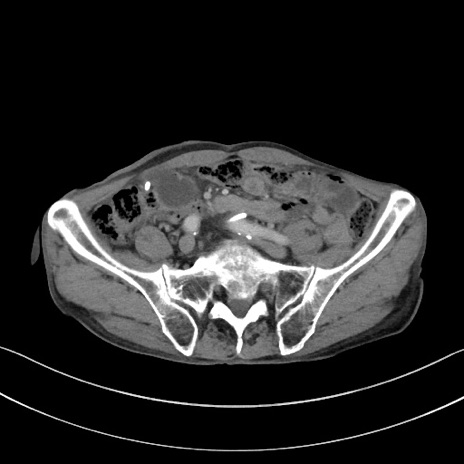

冠状断像

【症例】 70歳代男性

【主訴】右鼠径部腫瘤、疼痛

【現病歴】本日朝より上記主訴あり、受診。

【既往歴】膀胱癌にて膀胱全摘、両側尿管皮膚瘻

【データ】WBC 5600、CRP 0.56